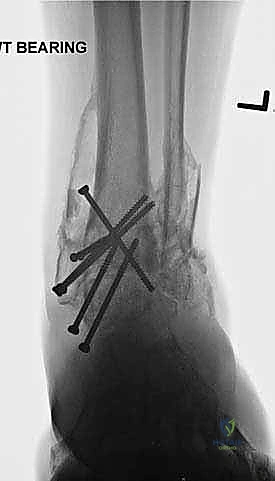

- الأشعة السينية أثناء الوقوف (Weight-bearing X-rays): هي الفحص الذهبي والأهم. يجب أن تؤخذ الأشعة والمريض واقف لتحمل الوزن. تظهر الأشعة تضيق المسافة المفصلية (دليل على فقدان الغضروف)، وجود نتوءات عظمية، تصلب العظم، وأي انحراف في محور المفصل.

- التصوير المقطعي المحوسب (CT Scan): يطلبه الدكتور هطيف لتقييم جودة العظام (Bone stock)، تحديد حجم الأكياس العظمية، ورسم خريطة ثلاثية الأبعاد للتشوهات المعقدة قبل الجراحة.

- التخطيط الجراحي الرقمي: باستخدام صور الأشعة المقطعية، يقوم الدكتور هطيف بتخطيط الجراحة على الكمبيوتر لاختيار حجم المسامير والشرائح المناسبة بدقة مليمترية.

خطوات جراحة تثبيت مفصل الكاحل الأمامي بالتفصيل (Step-by-Step Surgical Procedure)

تُجرى العملية تحت التخدير العام أو النصفي (الشوكي)، وتستغرق عادةً بين ساعتين إلى ثلاث ساعات، وتتطلب دقة ومهارة فائقتين. إليكم الخطوات الجراحية كما ينفذها الأستاذ الدكتور محمد هطيف: